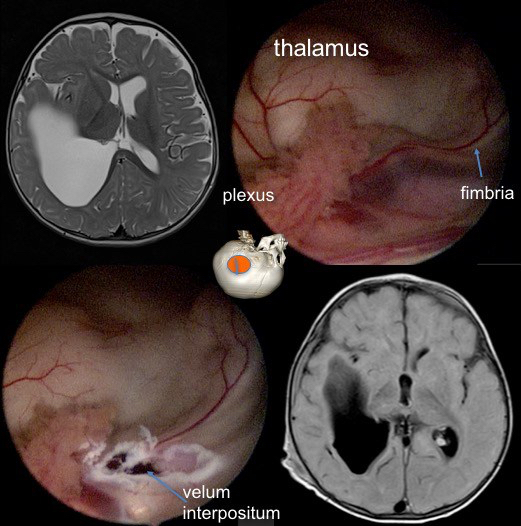

kyste du plexus choroïde

ces kystes sont très fréquents en anténatal, mais nécessitent très rarement un traitement chirurgical ; la fenestration endoscopique est le traitement le mieux adapté.

visionner l’endoscopie pour kyste du plexus choroïde